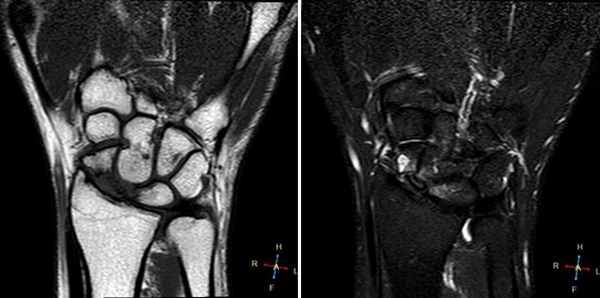

(Слева) МР-артрография в режиме Т1ВИ, коронарный срез: визуализируется крупный дефект ЛПС. Суставная щель расширена. Следует отметить наличиедегенеративных перфораций в центральной части ТФХК.

(Справа) МР-артрография в режиме Т2ВИ FS, коронарный срез: визуализируется крупный дефект ЛПС. Суставная щель расширена. Следует отметить неравномерное истончение хряща и кистозные изменения суставных поверхностей, обусловленные нестабильностью. Это говорит о том, что разрыв данной связки был биомеханически значим. (Слева) Артрография в заднепередней проекции: распространение контрастного препарата через дефект ЛПС в среднезапястный сустав. ПТС интактна.

(Справа) МР-артрография в режиме Т1ВИ, коронарный срез, этот же пациент: визуализируется интактный тыльный пучок ЛПС. Разрыв мембранозной порции на данном срезе не виден (располагается кпереди). Разрыв центральной мембранозной порции ЛПС часто протекает бессимптомно. (Слева) Непрямая МР-артрография в режиме Т1ВИ FS с КУ, коронарный срез: визуализируется значительное расширение ладьевидно-полулунного промежутка. Отмечаются признаки артрита лучеладьевидного сустава. Головчатая кость смещена проксимально в промежуток между ладьевидной и полулунной костями. Картина характерна для ПЛПК запястья.

(Справа) МР-артрография в режиме PD FS, сагиттальный срез, этот же пациент: определяется разрыв восстановленного фрагмента связки, имеющего аморфную структуру и неровный контур. Полулунная кость отклонена в тыльную сторону, что позволяет заподозрить ТНПС. Положение полулунной кости должно быть сопоставлено с осью ладьевидной кости на соседних срезах.